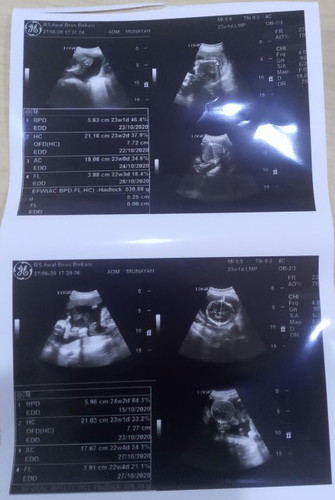

Assalamualaikum,para bunda... Mohon maaf sebelumnya, bukannya saya mau pamer tapi saya hanya ingin berbagi kebahagiaan... Umur kandungan saya 23w,dan selama ini saya hanya memeriksa di bidan dekat rumah saja. Akhirnya kemarin sore saya memeriksa kandungan saya dan di USG... Betapa terkejutnya saya,saya di beritahu bahwa saya memiliki janin kembar, Syukur Alhamdulillah,,saya kaget,senang bercampur aduk semua rasa. Kenapa saya kaget,karena riwayat dari saya dan suami maupun kedua keluarga besar kami tidak ada yang hamil kembar.. Dulu sempat kepikiran bahwa janin saya dua, tapi saya tepis karena di keluarga kami tidak ada kembar. Dan ternyata syukur Alhamdulillah saya mendapatkannya... Rasanya seperti mimpi... Buat para bunda di sini,, Semoga yang masih berusaha untuk promil di segerakan mendapatkan momongan... Semoga yang dag Dig dug menunggu HPL,di beri kelancaran sampai Dede bayinya lahir kedunia... Semoga kita semua di berikan kesehatan sampai waktunya untuk melahirkan.... Aamiin aamiin ya rabbal alamin...

one princes one prince